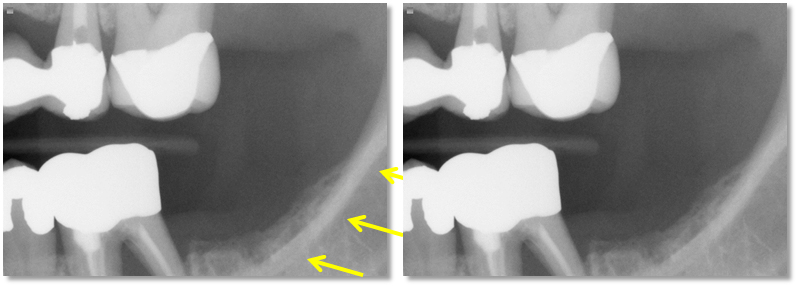

what causes ghost images

glasses, jewelry, retainers, etc

why do open lips cause an error in a pano

makes dark radiolucent shadows in anterior region

why tongue not on hard palate matter

radiolucent shadows will appear around the apices of maxillary teeth